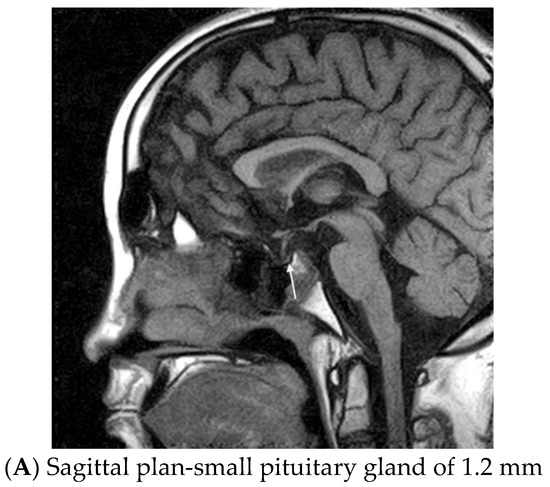

Based on the clinical and lab data, the following diagnosis was established: secondary hypothyroidism, hypogonadism and adrenal insufficiency and short stature, most probably as elements of post-TBI hypopituitarism. Central nervous system magnetic resonance imaging (MRI) with contrast media confirmed post-traumatic aspects: a small pituitary gland (~1.2 mm), right deviated pituitary stalk with neurohypophysis in addition to other post-traumatic brain lesions like discontinued right optic nerve, para-sphenoidal herniation of the arachnoid (Figure 2).

Figure 2.

Magnetic resonance imaging on a 17-year-old male with post-brain trauma injury, 4 years after a severe car accident.